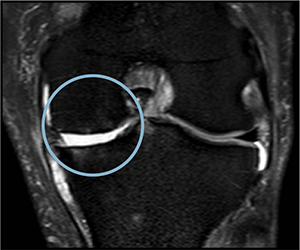

Before starting cell therapy, patients undergo a magnetic resonance imaging (MRI) or computed tomography (CT) scan to assess the condition of the bone and soft tissues of the knee.

The initial therapeutic strategy will include a minimum of three applications over a period of six months. Control images will be taken after this period to evaluate the process. If deemed necessary, the treatment can be repeated.Patients will normally start seeing improvements 3-4 weeks after treatment. This means less pain and better movement.